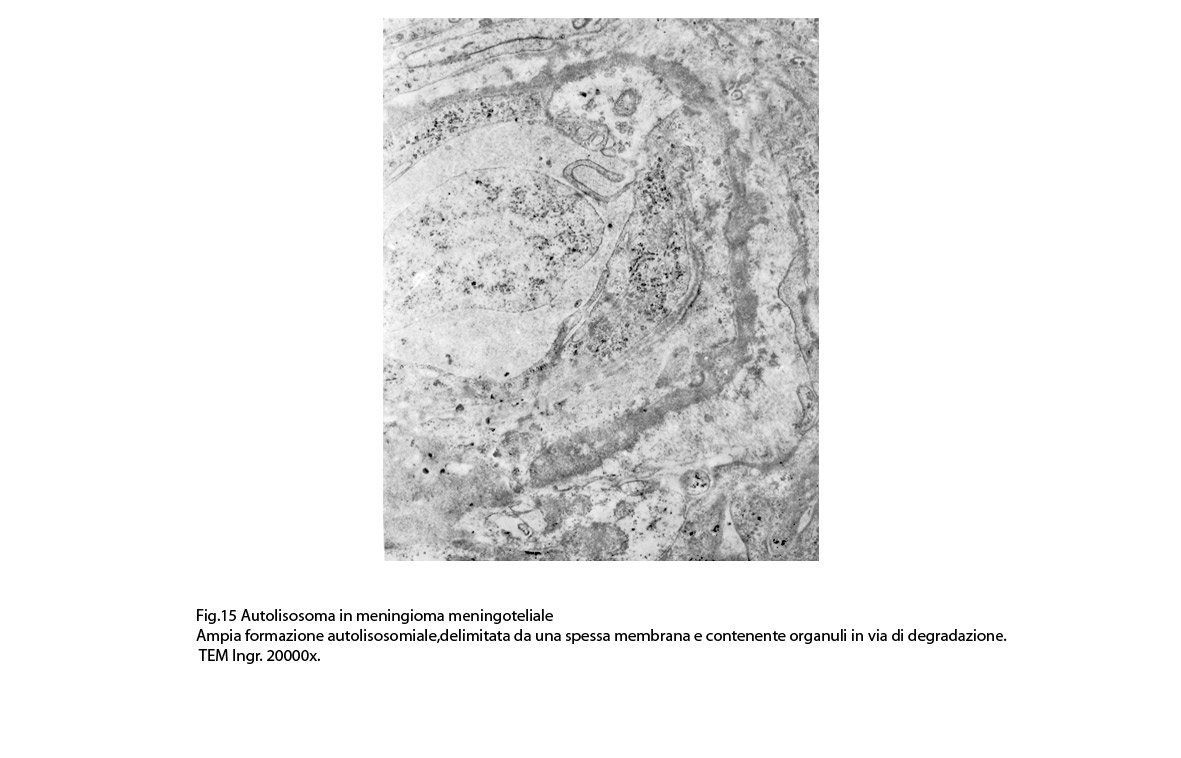

Non è raro il riscontro di cellule meningoteliali le quali hanno il citoplasma in buona parte occupato da una formazione cava,irregolarmente rotondeggiante; questa è delimitata da una spessa membrana ed è occupata da frammenti di citoplasma e da singoli organuli,tutto in corso di degradazione.